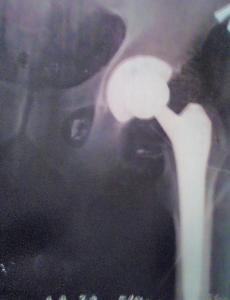

Приветствую. Мне делали - левый меняли в 15 году - в 1 градской  больнице г Москвы. По знакомству доктор не советовал ставить керамику ( платный - тогда стоил около 200 т р)- т к скрипеть будет со временем. Мне поставили бесплатный - штатовский -  по квоте и по знакомству ставили - 5 лет - полет нормальный.   Коротко операция 2-3 часа, наркоз в спину, не спишь - я кашлял всю операцию. Ни чего не чувствуешь только все слышишь - и запах пиленной кости чувствуешь. Самое не приятное отходняк и первые сутки - обезболивающее колют обычное - наркоту не дают - мне при первой операции ( скоба на позвоночнике стоит) давали - весь отходняк проспал. А здесь ощущение не из приятных. На второй день стал на костыли - во вторник сделали - в пятницу домой уехал. Потом пол года упражнения и велотренажёр- по дому на костылях прыгал- чтоб не нагружать сразу.

image.thumb.jpeg.b10113247a1dd92cf9a2868bcdf12e3b.jpegimage.thumb.jpeg.5c54488d9da7d09f849a670c593400a5.jpeg